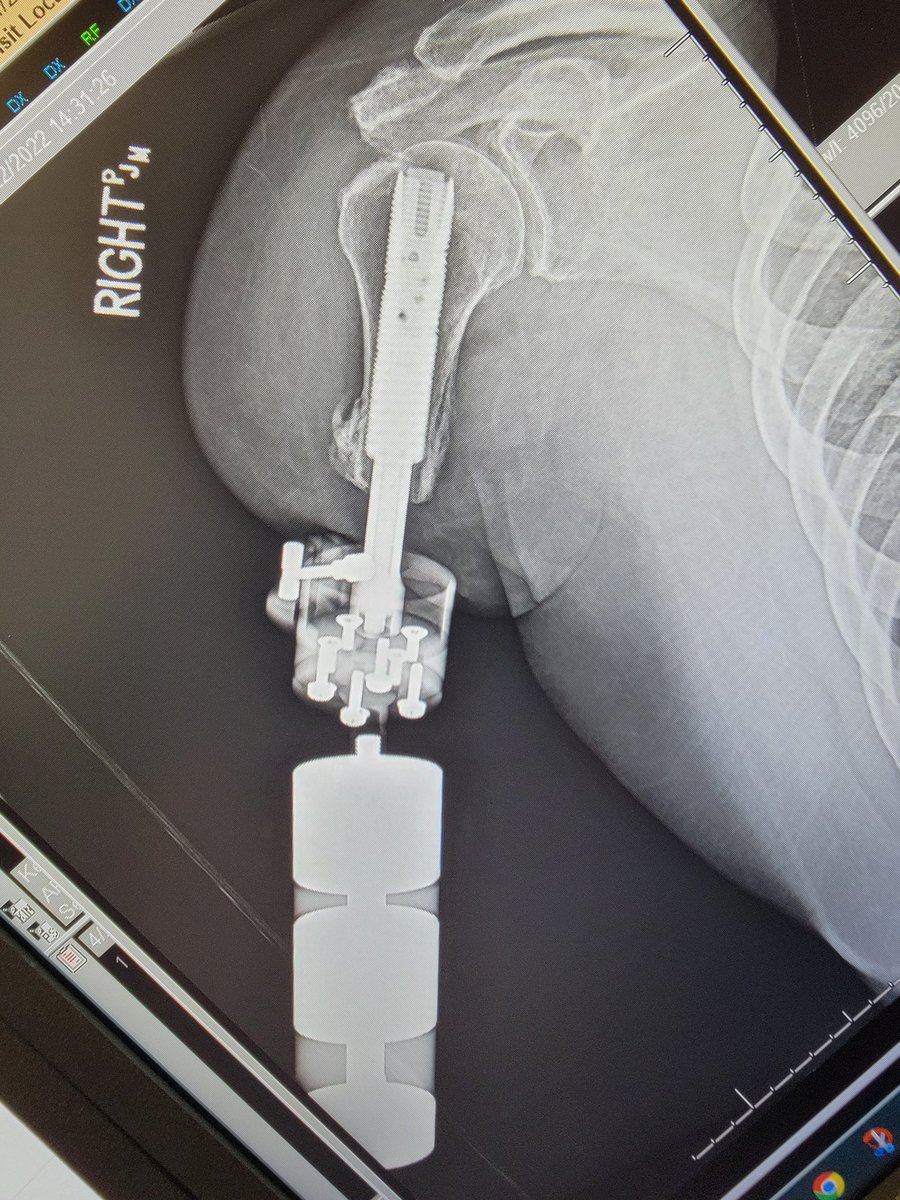

**With permission** Thank you Ron5Toes for sharing with our LLRS traveling fellows! #limblengthening followed by #osseointegration #orthotwitter olivia-rice16 @DrMarecek CLTOsseointegration

Thank you Tony for sharing your journey. You are an inspiration! youtube.com/watch?v=JobFtF… #osseointegration #amputation #uplift Atrium Health Musculoskeletal Institute Atrium MSKI Research (CMC) CLTOsseointegration OTA AAOS LLRS CMC Ortho Trauma Fellowship (Atrium Health)

After losing both legs in a work-related accident, Tony Cordell thought he’d never walk again. Thanks to an innovative new prosthetics treatment called osseointegration performed at Atrium Health Musculoskeletal Institute, Tony is walking again ⤵️ spr.ly/6013MUR6N